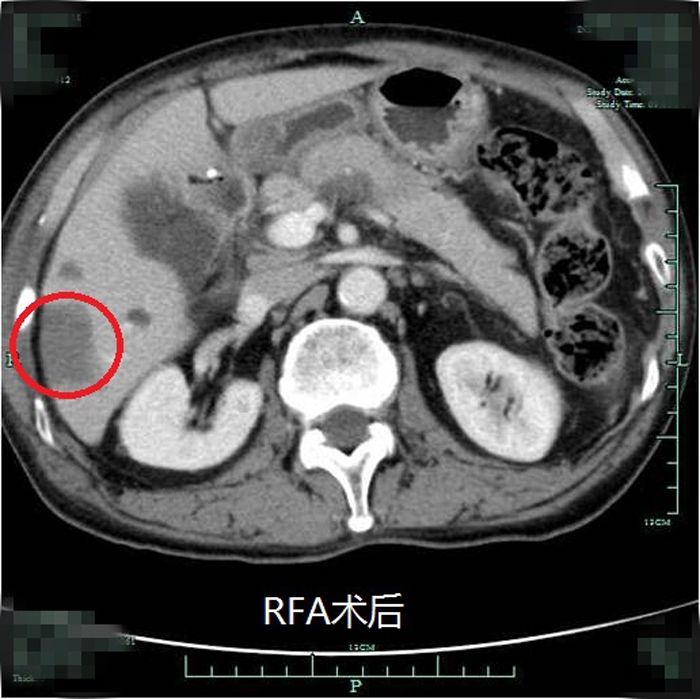

典型射頻治療患者術(shù)前術(shù)后效果對(duì)比(非該尾狀葉患者)

??? 近年來,我院肝膽外科在肝癌治療的綜合體系方面更加合理完善,肝癌射頻消融術(shù)已逐步成為繼肝癌切除術(shù)、經(jīng)皮選擇性肝動(dòng)脈栓塞化療(TACE)后常規(guī)開展的治療手段。自2012年開展此項(xiàng)技術(shù)以來,針對(duì)常規(guī)部位的肝癌射頻消融均取得了非常理想的效果。但由于尾狀葉腫瘤位置較深,周圍大血管包繞,不僅手術(shù)難度大,能否安全徹底地對(duì)該部位腫瘤進(jìn)行射頻消融也具有一定的挑戰(zhàn)性。此次在超聲影像等多學(xué)科的團(tuán)隊(duì)協(xié)作下,成功完成了尾狀葉腫瘤的射頻消融術(shù)。